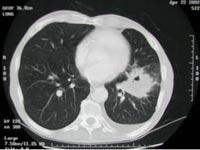

问题 男性患者,78岁,吸烟50余年,近1年来常干咳,来院就诊时行胸部CT检查,结果如图所示,最有可能的诊断是 ( )

选项 A、右肺癌 B、以上均不正确 C、肺结核 D、左肺癌 E、支气管扩张

答案 D